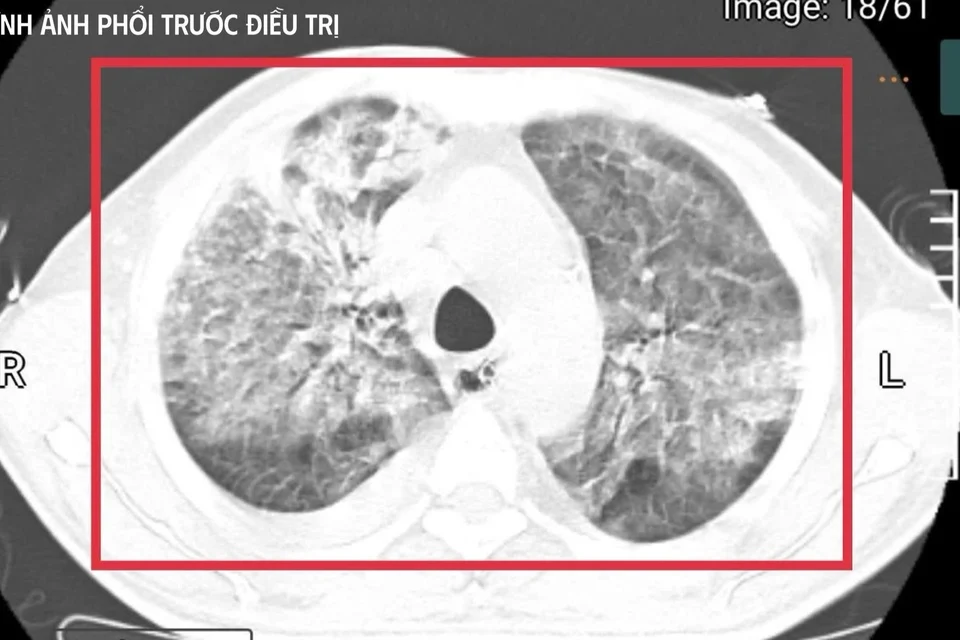

Hình ảnh phổi của bệnh nhân trước khi điều trị. (Ảnh: BVCC)